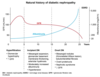

what is the histopathological change seen in diabetic nephropathy

what is the finding